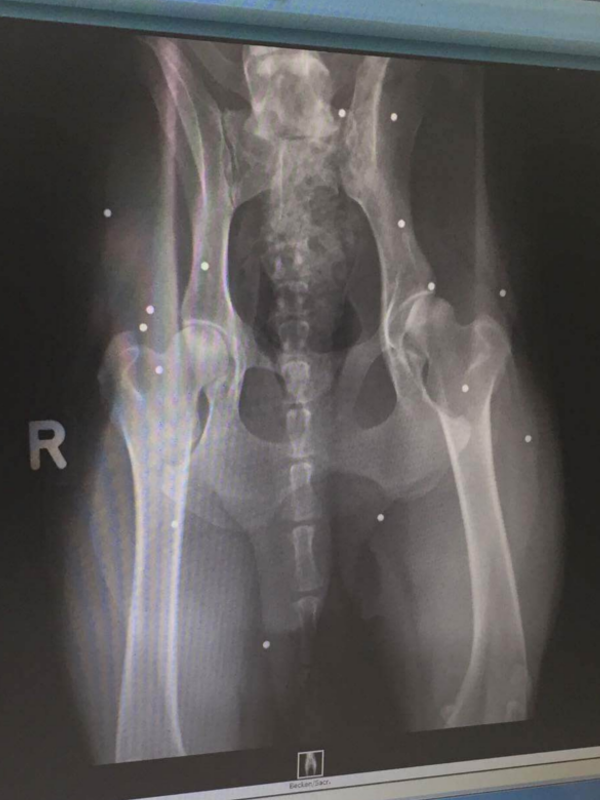

Seule une visite chez le vétérinaire leur a permis d’enfin nettoyer Tara. Celle-ci a été anesthésiée, puis examinée avec soin. Le couple a alors fait plusieurs découvertes. Tara n’avait pas un an, mais quatre. Elle n’était donc pas du tout un chiot, comme on le leur avait dit précédemment.Mais la découverte la plus choquante est venue par l’intermédiaire de radios. Le corps de Tara était criblé de 14 balles. Esther confie:

J’ai commencé à pleurer quand j’ai vu les radios. C’était le chien le plus adorables du monde, ce qui est dur à croire quand on connaît ce qu’elle a vécu. Tout ce qu’elle veut, c’est que tout le monde soit heureux.